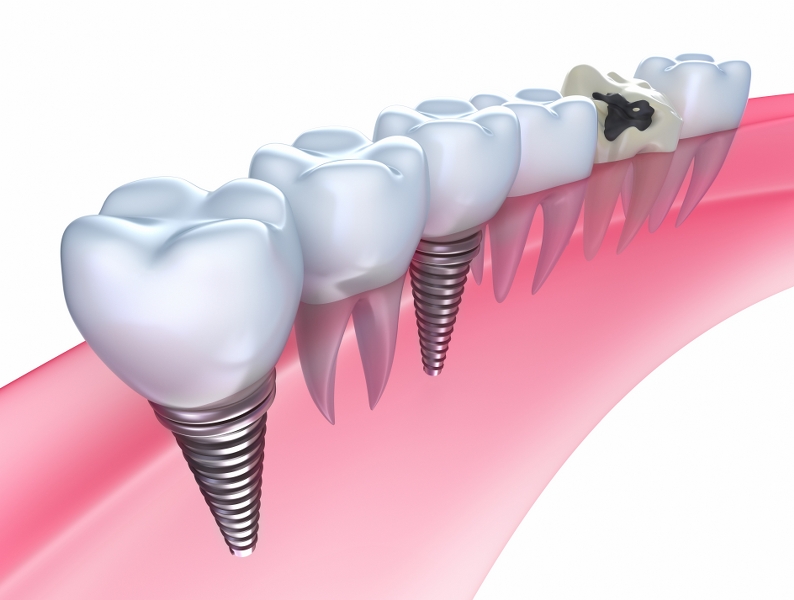

Современная стоматология: Железные зубные импланты